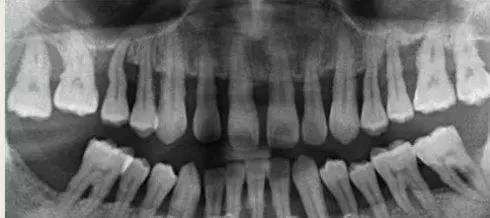

牙龈炎与牙周炎的区别 1、牙龈炎仅仅是龈组织的炎症,出现红肿、点斑消失;而牙周炎不仅出现牙龈的炎症,还包括整个牙周组织的炎症。 2、牙龈炎没有骨的破坏,所以X线片上没有骨吸收的情况。而牙周炎X线片上可见牙槽嵴的高度降低,呈水平型吸收,也可出现近牙根面的牙槽骨吸收,呈垂直或角形骨吸收,这种骨的吸收,临床上表现为骨下袋。 3、牙龈炎不会导致牙齿松动,而牙周炎后期可出现牙齿移位和松动。 4、牙龈炎虽然由于牙龈红肿,可使龈沟加深,但牙龈炎不会形成牙周袋。而牙周炎由于牙龈纤维变性破坏、结合上皮向根方增殖而形成牙周袋。 当然,如果你没法判断自己是牙龈炎还是牙周炎,建议到专业口腔机构检查一下,医生会根据口腔情况提供具体的治疗措施。